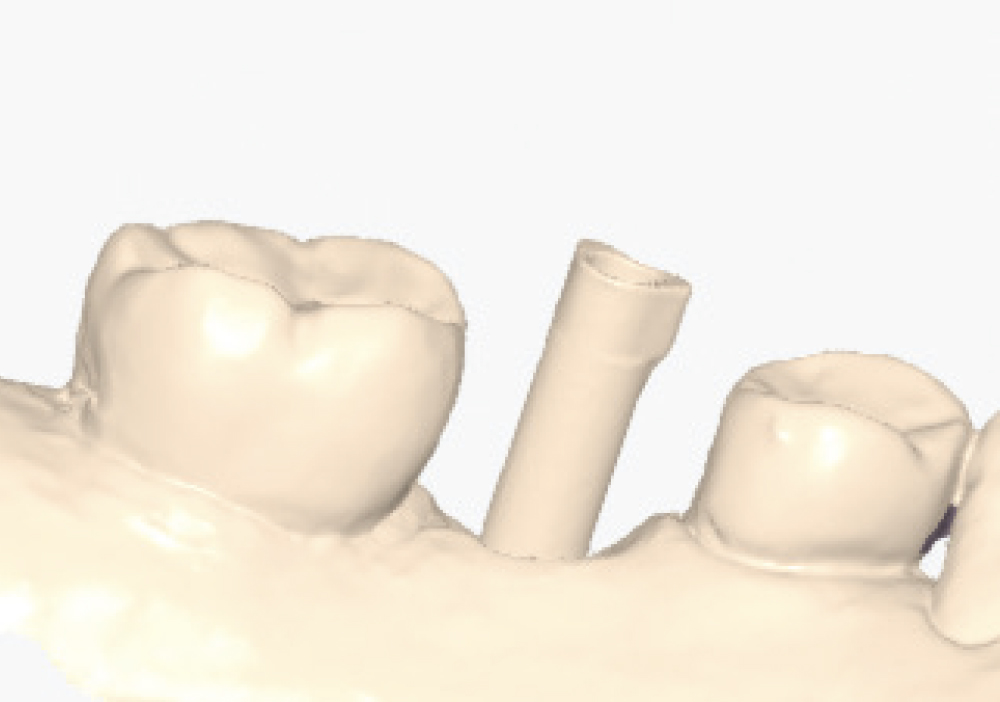

Implant post scan on left side of mouth

Implant post scan pointing down

Implant post scan close up

Verify the Scans Before Dismissing the Patient. Review all critical areas while the patient is still in the chair, ensuring complete scan body capture, accurate contacts, adequate tissue detail, and proper bite registration. Zoom in on critical areas to verify resolution and completeness. It takes only two minutes to verify a scan, but potentially days before a patient is able to return to your practice. Use the scanner’s analysis tools to identify distortions or artifacts.